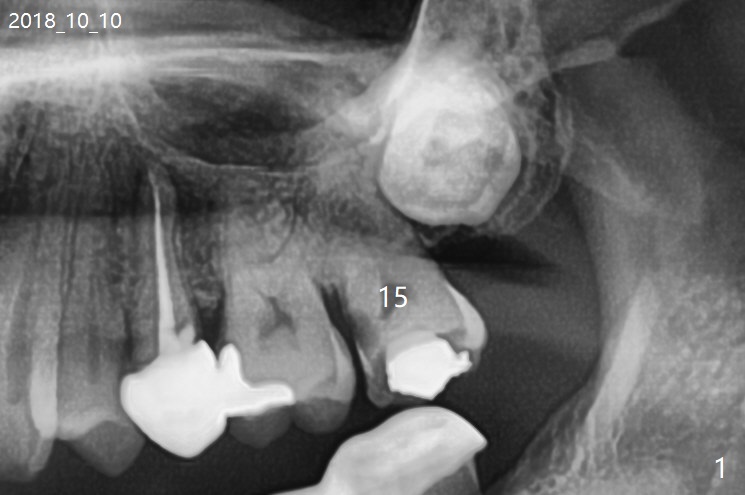

A 62-year-old man returns with acute pulpitis at #15 (Fig.1,2). The caries is confirmed subgingival after debridement. After discussion, the patient agrees with extraction and bone graft, but he does not want to have implant (Fig.3). When he changes his mind, the 3rd molar will be extracted immediately followed by implant placement with guide. Because of the narrow space, the distal surface of the distobuccal root of the 1st molar is exposed when the tooth #15 is extracted. The bone graft will prevent gingival recession of the tooth #14.